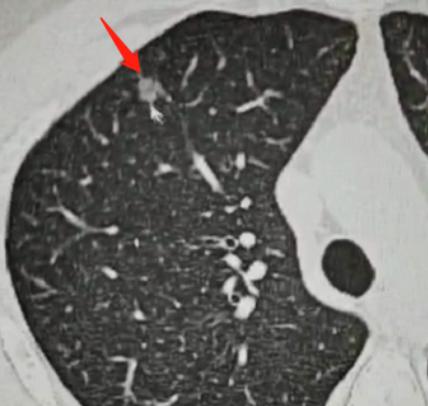

这位33岁的女性患者,体检发现右肺有2个磨玻璃结节,可以清楚地看到,这两个结节与